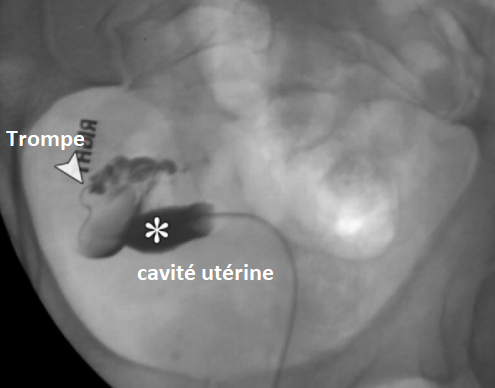

Utérus Unicorne

variations variante utérine DES Diethylstilbestrol malformation hypoplasie agénésie unicorne didelphys didelphe unicornate corne cornes septa septas septé septation arcuate acruate arqué DES médicamenteux anomalies de Muller mullarian

variations variante utérine DES Diethylstilbestrol malformation hypoplasie agénésie unicorne didelphys didelphe unicornate corne cornes septa septas septé septation arcuate acruate arqué DES médicamenteux anomalies de Muller mullarian